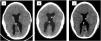

ResultsThe median age at first shunt was two months (0–67). The mean number of shunt revisions before inclusion was three. Shunt removal was attempted in seven patients without success; temporary success was observed in two patients who underwent ETV. Two patients had previous cranial expansions. The mean age at inclusion was 9.1 years (2.7–15.2). After the shunt system was exchanged and upgraded, clinical improvement was observed in 94.4% (17/18) of patients, and radiological improvement was observed in 83.3% (15/18) of patients. The median follow-up was 21 months.